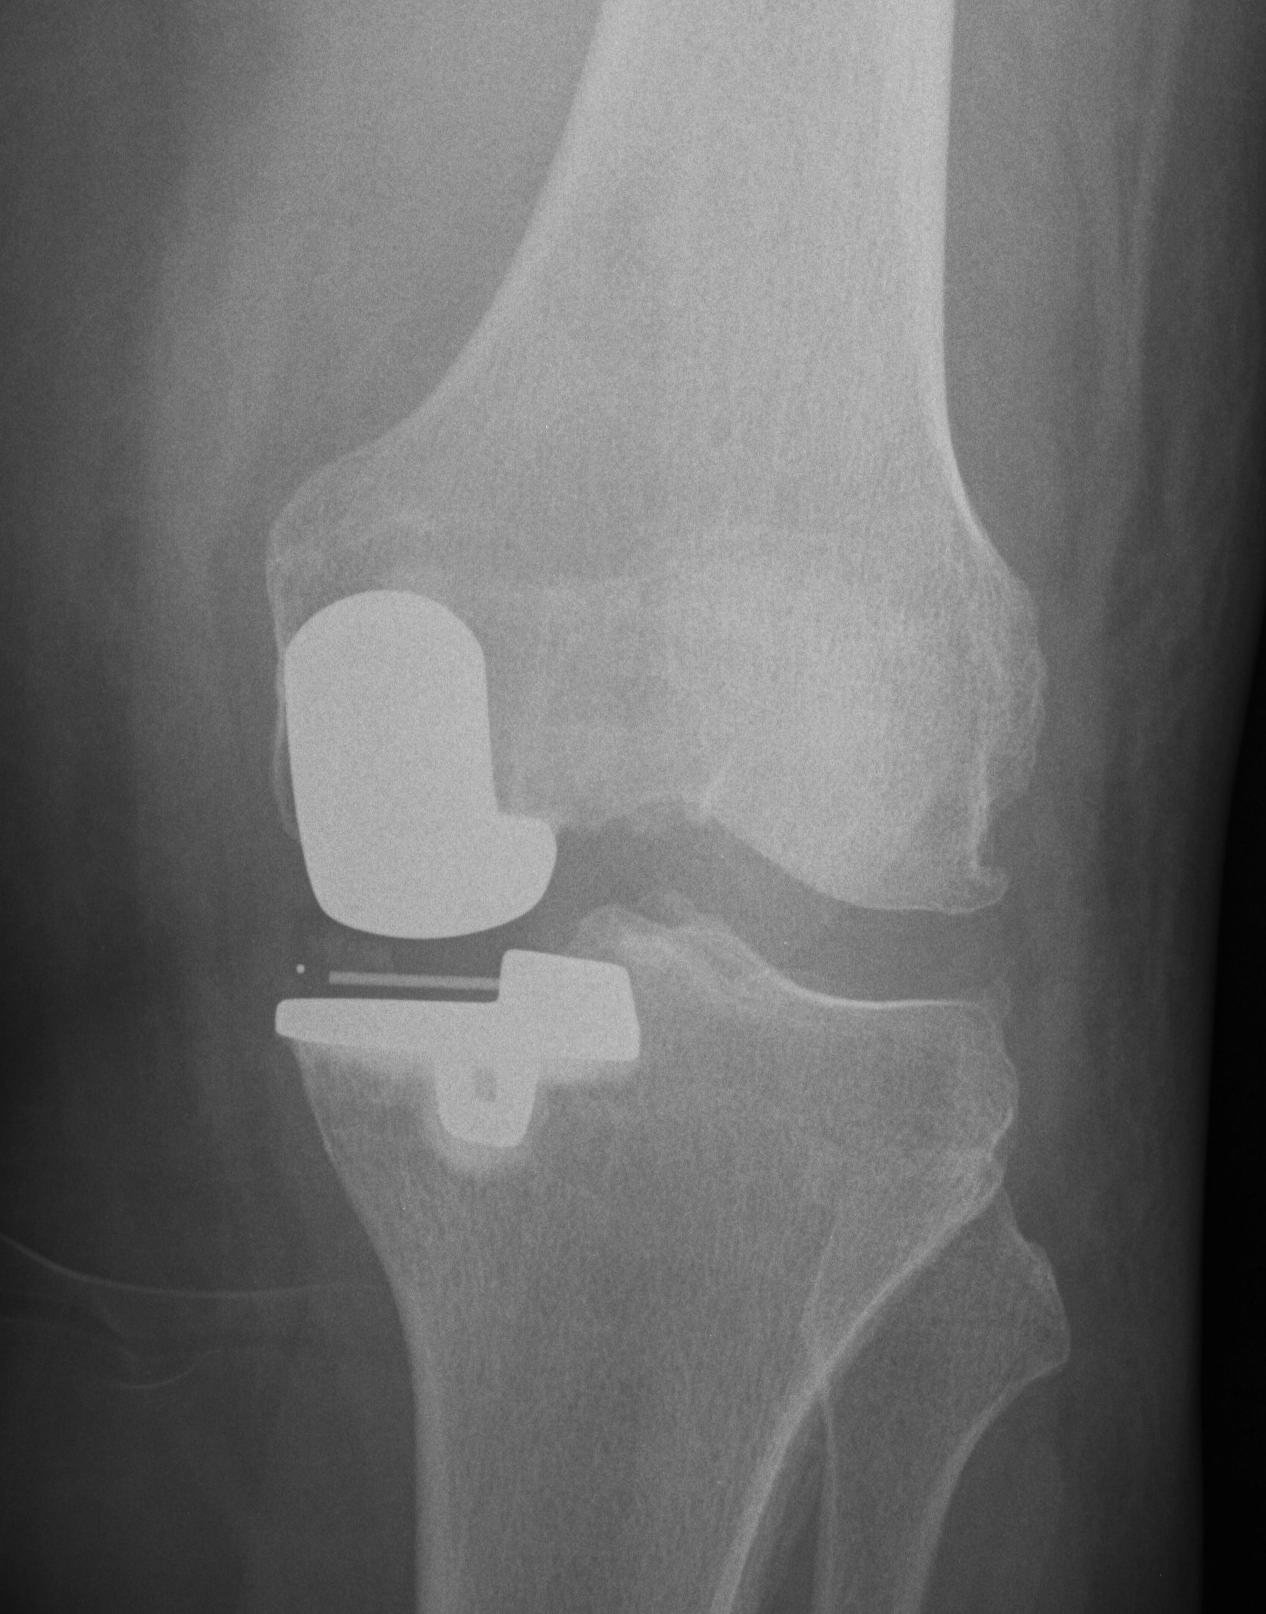

Pre-op x-rays

- AP and lateral